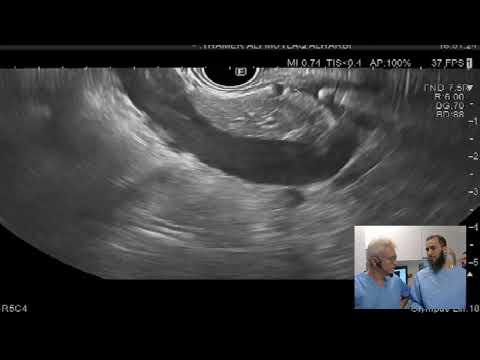

Frances Dang, MD, MSc, et al present a novel use of absorbable gelatin sponge slurry for hemostasis during EUS-guided liver biopsy and propose a stepwise management approach. DOI: